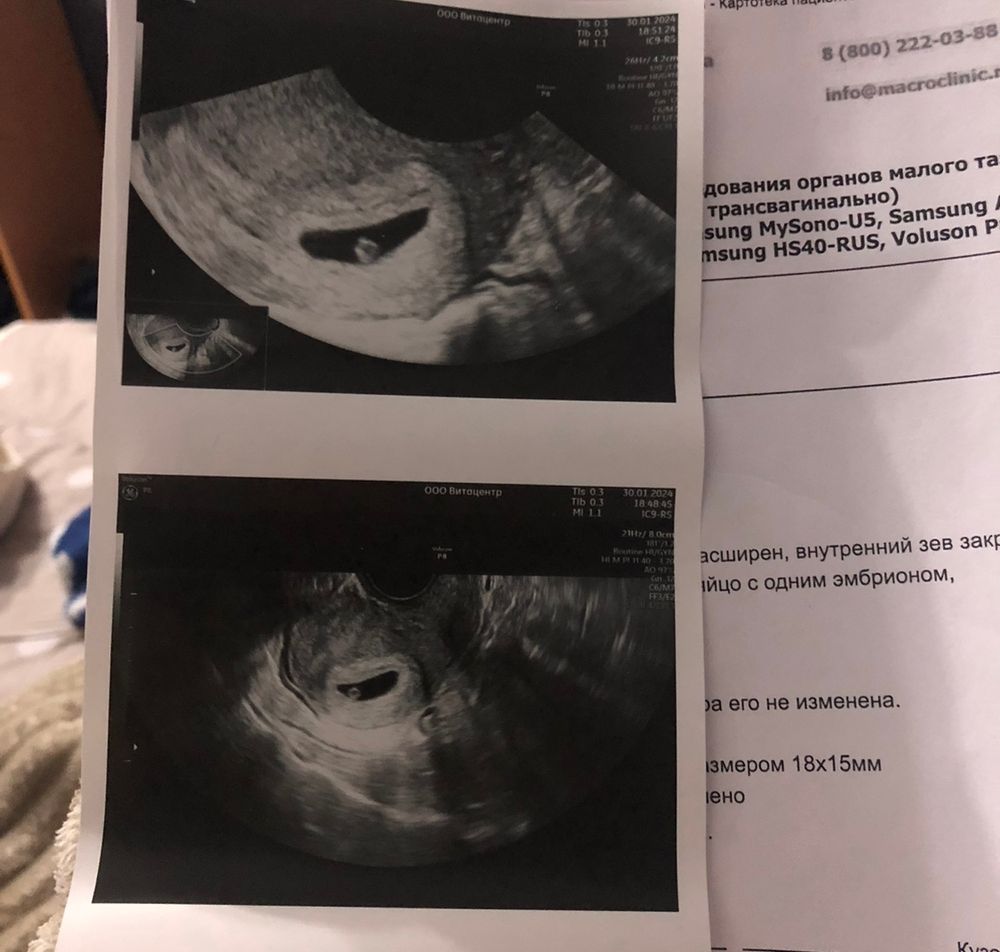

Киньте плз фото вашего УЗИ 5-5,5 недель

УЗИ, КТГ, доплерХочу посмотреть как оно должно "нормально" выглядеть 🙏🏻

Алена, 2 дня назад мне по УЗИ доктор предположил 5 с чем-то недель, фото УЗИ не дал, но мне визуально показалось что желточный мешок большой какой-то. Хочу понять, может так и должно выглядеть